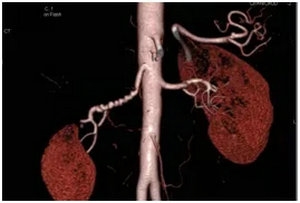

CTA重建:串珠样改变

以上是纤维肌发育不良的主要的影像学检查手段,典型的“串珠征”是特异性的影像学征象。